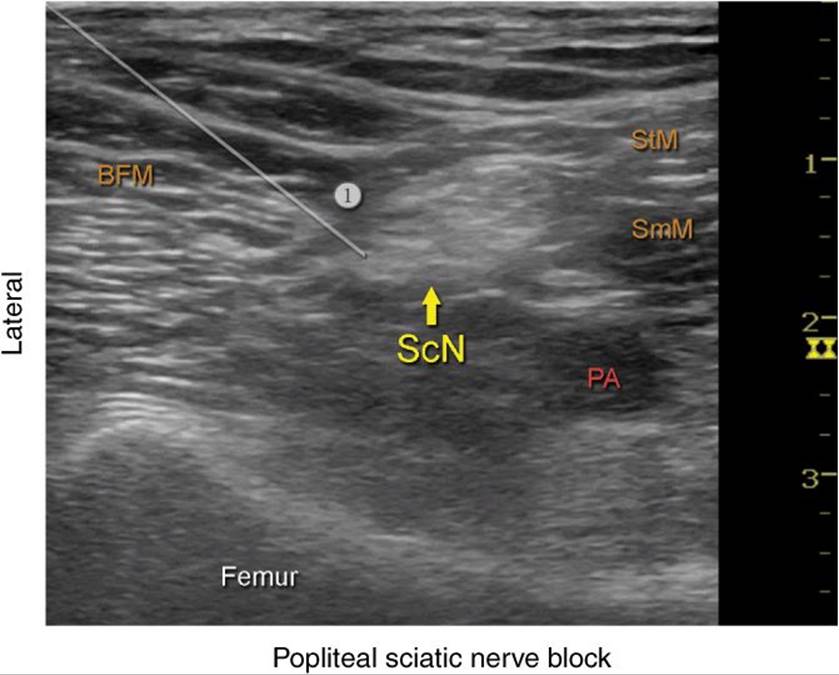

Ultrasound guide

Ultrasound guide 108 фотографий